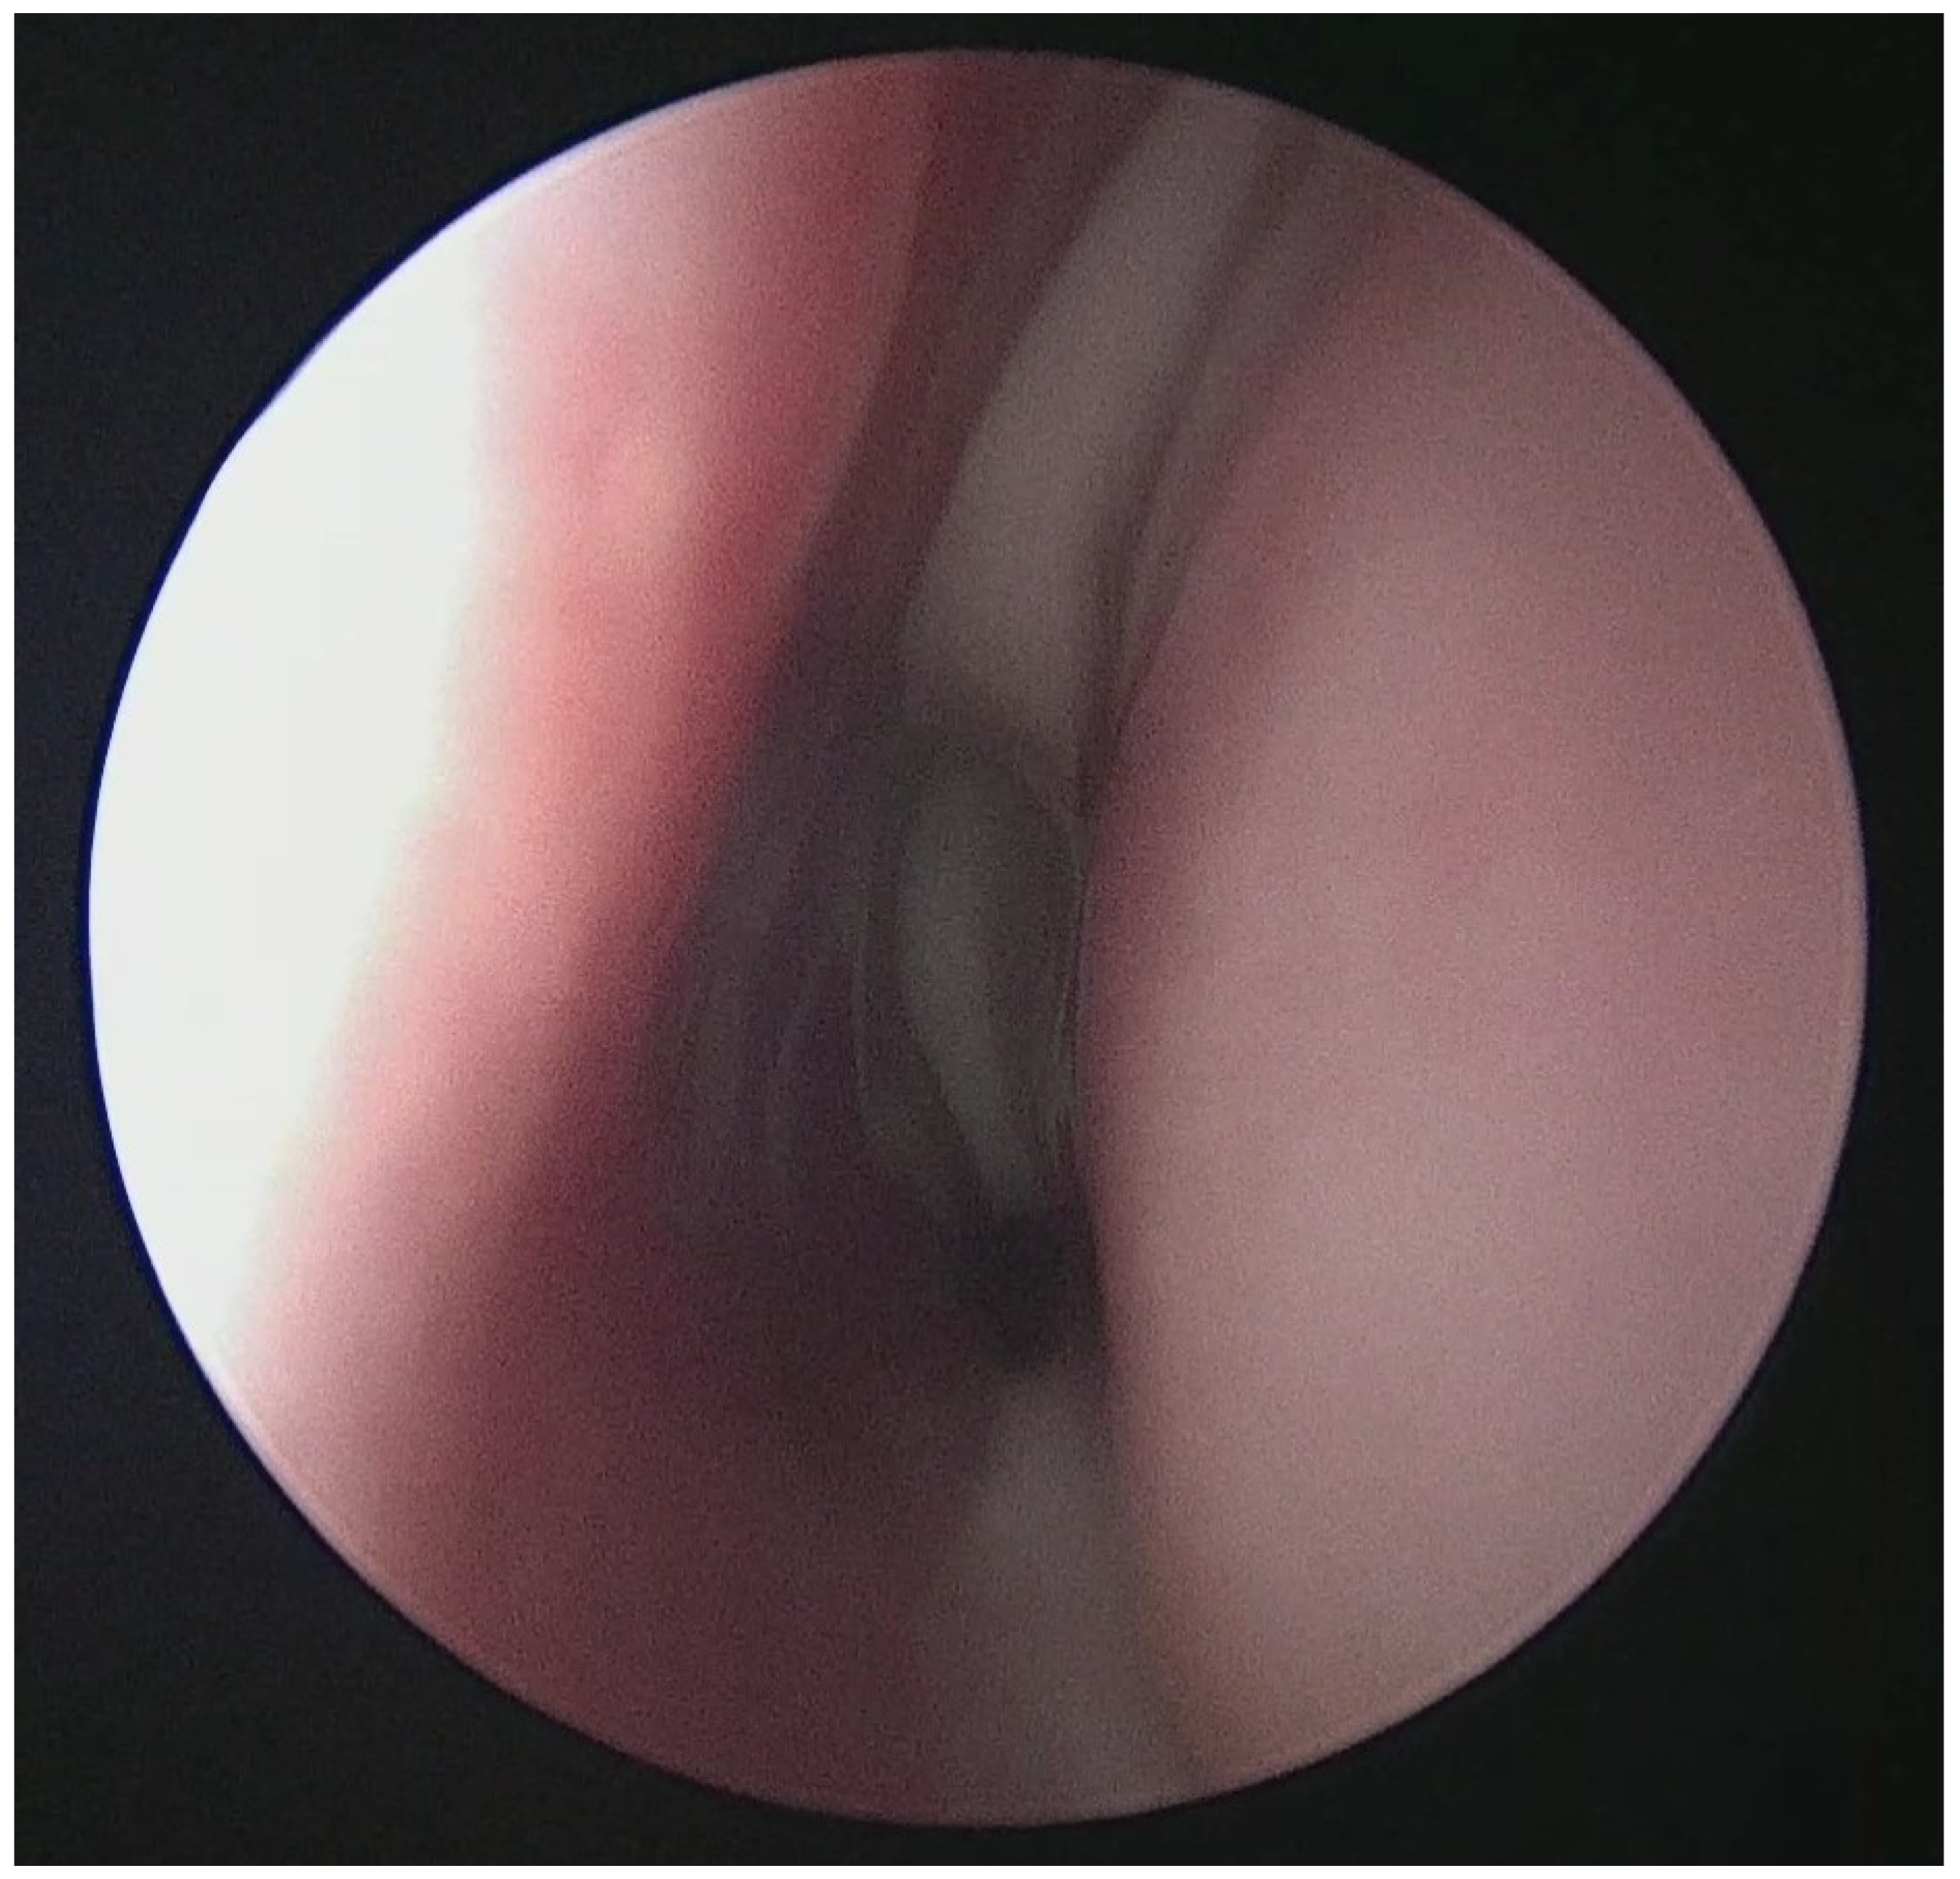

Figure 2. Mucopurulent discharge in nasal cavity upon nasoendoscopic examination.